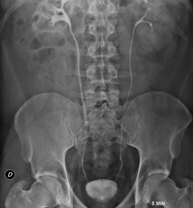

- RX Abdomen

Tècnica que usa els raigs X a través de la qual s'obtenen imatges de l'abdomen (estómac, intestí prim, intestí gros, fetge, ronyons, bufeta, pelvis òssia, etc.) per al seu estudi. - RX Columna lumbar